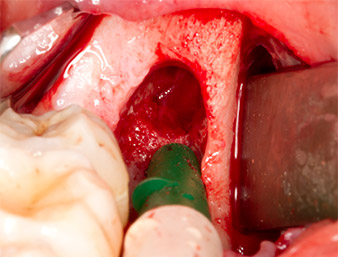

Um autogenes Material für die spätere Wundversorgung zu gewinnen, wurden mit einem piezochirugischen Instrument (Piezomed B5) gesunde Knochenspäne aus der Umgebung des Wurzelrests gewonnen (Abb. 5).

Das autogene Gewebe wurde mit dem schaufelförmigen Arbeitsteil des Instruments entnommen und bis zur weiteren Verwendung in physiologischer Kochsalzlösung aufbewahrt (vgl. Abb. 13).